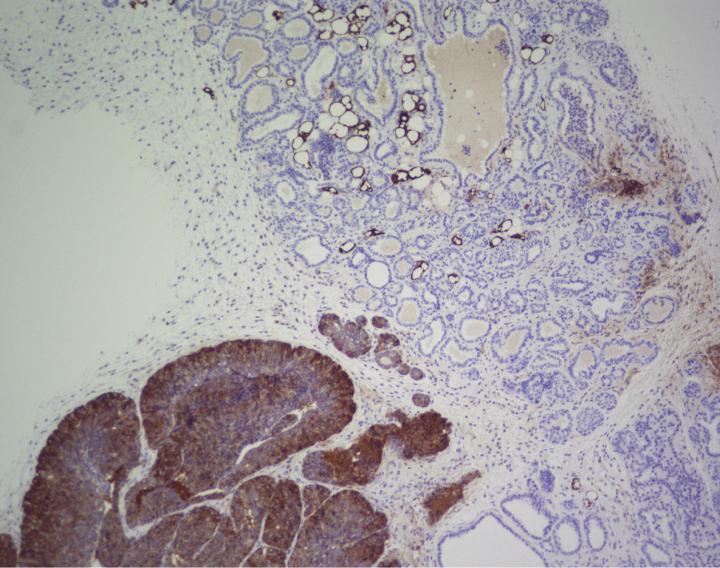

Researchers around the world are studying the potential of FASN to treat certain types of cancer. However, the results of the CNIO team suggest that its effectiveness is preventive, not therapeutic. "In our mouse model, which develops a highly penetrant form of breast cancer, areas where FASN was present developed cancer, whereas tumours did not develop in areas where we blocked FASN, and survival increased by 68%," says Quintela. "But when we tried to inhibit FASN in already established tumours, there was a small transient effect that hardly affected tumour progression."